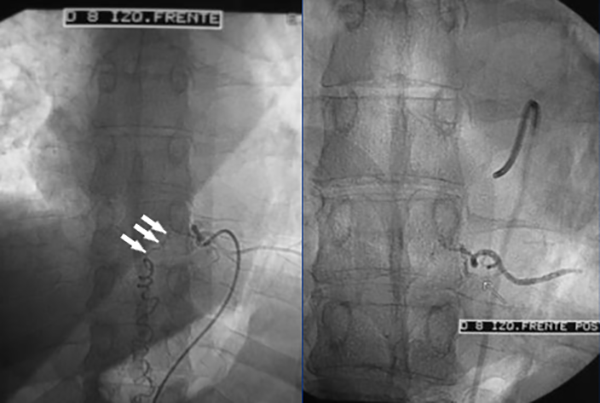

Figura 5: Caso #1. ADM mostrando la FDAVE en D8 izq. antes y después de la embolización. En la imagen de la izquierda (pre-embolización) las flechas blancas muestran la vena de drenaje de la FDAVE desde el punto fistuloso (más lateral) hacia medial en forma descendente y llegando a la línea media en donde se anastomosa con la vena espinal posterior y continúa hacia abajo en forma serpiginosa. La foto de la derecha (post-embolización) dejó de observarse la vena de drenaje y la vena espinal posterior (oclusión total de la FDAVE).

Figura 6: Caso #1. FDAVE recanalizada a los 15 meses post-embolización. ADM de frente (izquierda) y de perfil (derecha) las flechas blancas muestran el trayecto ascendente de la vena de drenaje. En el perfil se observa además que la vena de drenaje es dorsal.

CASO #1. Paciente masculino de 52 años con una historia de 6 meses de evolución de disestesias en ambos miembros inferiores, inestabilidad en la marcha, hiperreflexia y urgencia miccional. Se estudió con RMN (Fig. 3), ARM (Fig. 4) y ADM seguida de embolización con oclusión total de una FDAVE D8 izq. (Fig. 5). Evolucionó sin déficit y a los 11 meses comenzó con la misma sintomatología previa a la embolización. Se estudió nuevamente y la ADM (Fig. 6) mostraba la recidiva de la FDAVE y fue derivada para microcirugía (Fig. 7). Luego de la cirugía evolucionó sin déficit, se realizó una ADM diferida (Fig. 8) y lleva 116 meses libres de enfermedad.